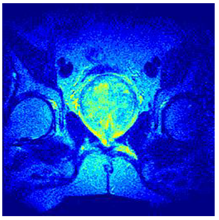

| Image | nt = 3 | nt = 4 | nt = 5 | nt = 8 |

|---|---|---|---|---|

| 1 | ![]() | ![]() | ![]() | ![]() |

| 2 | ![]() | ![]() | ![]() | ![]() |

| 3 | ![]() | ![]() | ![]() | ![]() |

| 4 | ![]() | ![]() | ![]() | ![]() |

| 5 | ![]() | ![]() | ![]() | ![]() |

| 6 | ![]() | ![]() | ![]() | ![]() |

| 7 | ![]() | ![]() | ![]() | ![]() |

| 8 | ![]() | ![]() | ![]() | ![]() |

| 9 | ![]() | ![]() | ![]() | ![]() |

| 10 | ![]() | ![]() | ![]() | ![]() |

| 11 | ![]() | ![]() | ![]() | ![]() |